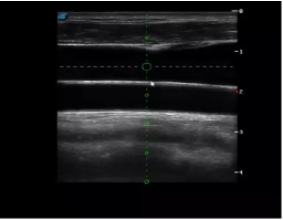

4  置管專用探頭

實時觀察穿刺針進入血管的全過程,方便操作及較短的穿刺路徑,智能進針尺寸提示,讓置管工作更加輕松,高效。

不同進針路徑